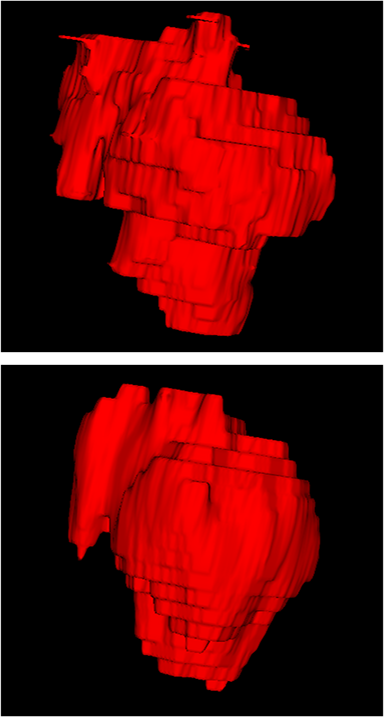

Comparison with related works. Table 1 reports the values of , and for different methods. Predicted masks of different methods are illustrated in Figure 9 and Figure 10, which respectively present results in 2D and 3D images. Through comprehensively analyzing these results, the proposed MMFNet actually have the following properties:

(i) It directly fuses 3D MRI images rather than 2D slices. Thus, it can effectively use meaningful information from neighboring slices of MRI to realize NPC segmentation. As shown in Table 2, MMFNet can bring , and improvements in and compared to the best method based on 2D images (Multi-modality patch-based CNN). And Figure 10 shows that 3D-based methods have less isolated regions (false positives) than 2D-based ones.